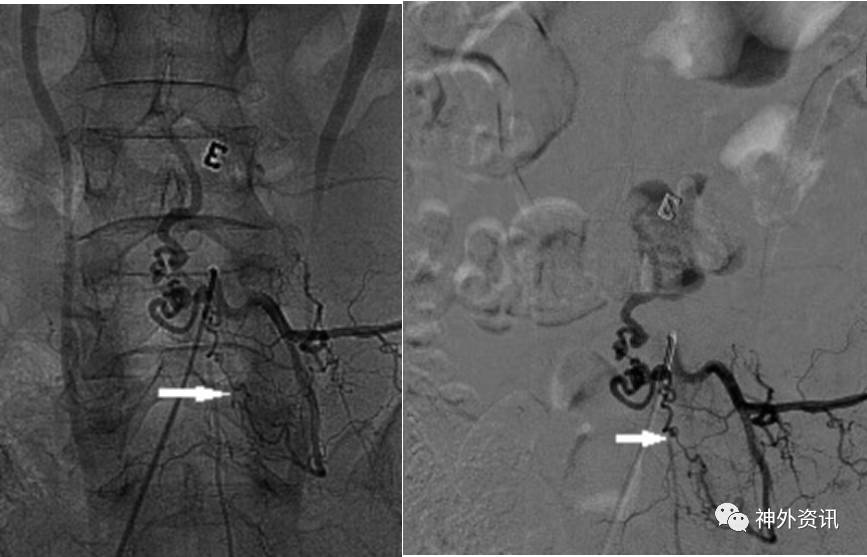

患者1年半前无明显诱因下出现双下肢乏力伴大小便功能障碍,无双下肢疼痛,无明显感觉障碍,未予重视。6月前患者双下肢无力加重,足背屈曲障碍,行走困难,大小便功能障碍较前进展,来我院就诊,查MRI检查提示胸椎-腰椎椎管内见迂曲增粗血管影,所示脊髓圆锥呈长T2信号(图1)。门诊拟“脊髓血管畸形”收住入院。

图1. MRI检查提示胸椎-腰椎椎管内见迂曲增粗血管影,所示脊髓圆锥呈长T2信号。